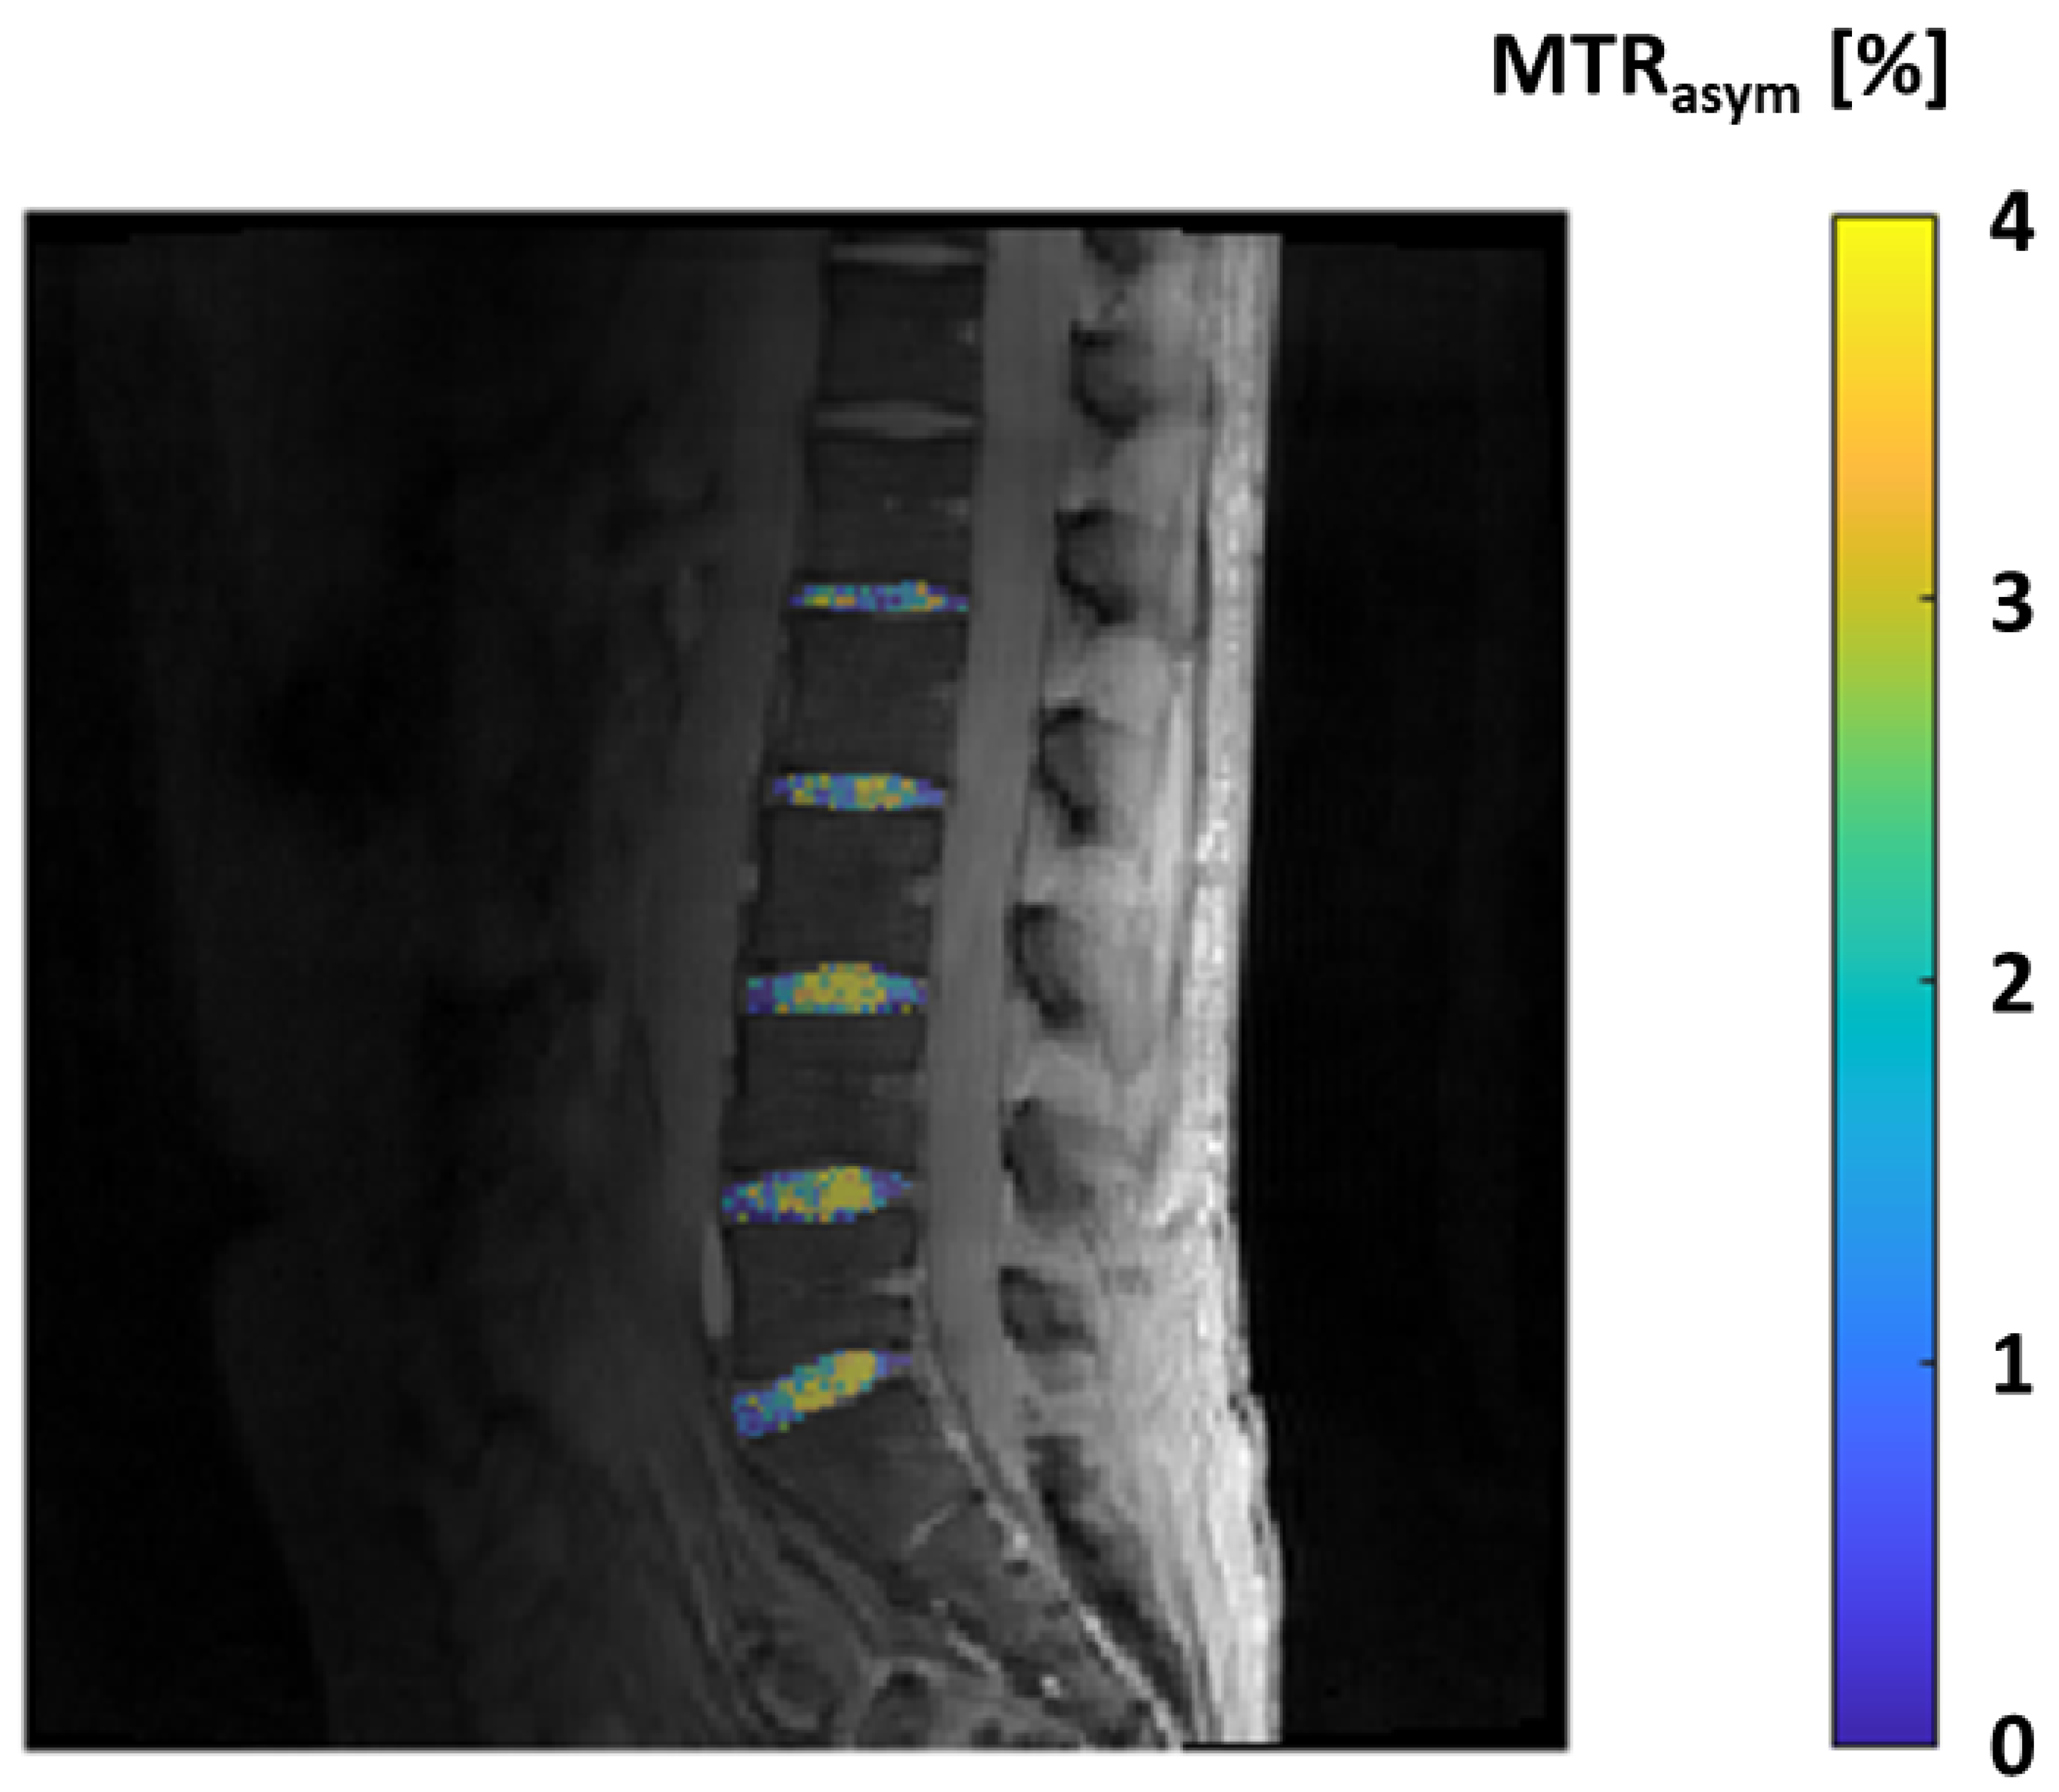

| GAG-CEST (glycosaminoglycan chemical exchange saturation transfer imaging) | Magnetization transfer (MT) | Direct quantification of GAG content. Promising for identification of initial knee-joint cartilage damage. Comparable to dGEMRIC and T2 mapping. Good to excellent reproducibility at 7T MRI. | High-field MRI (3T or more). Not yet well validated. |